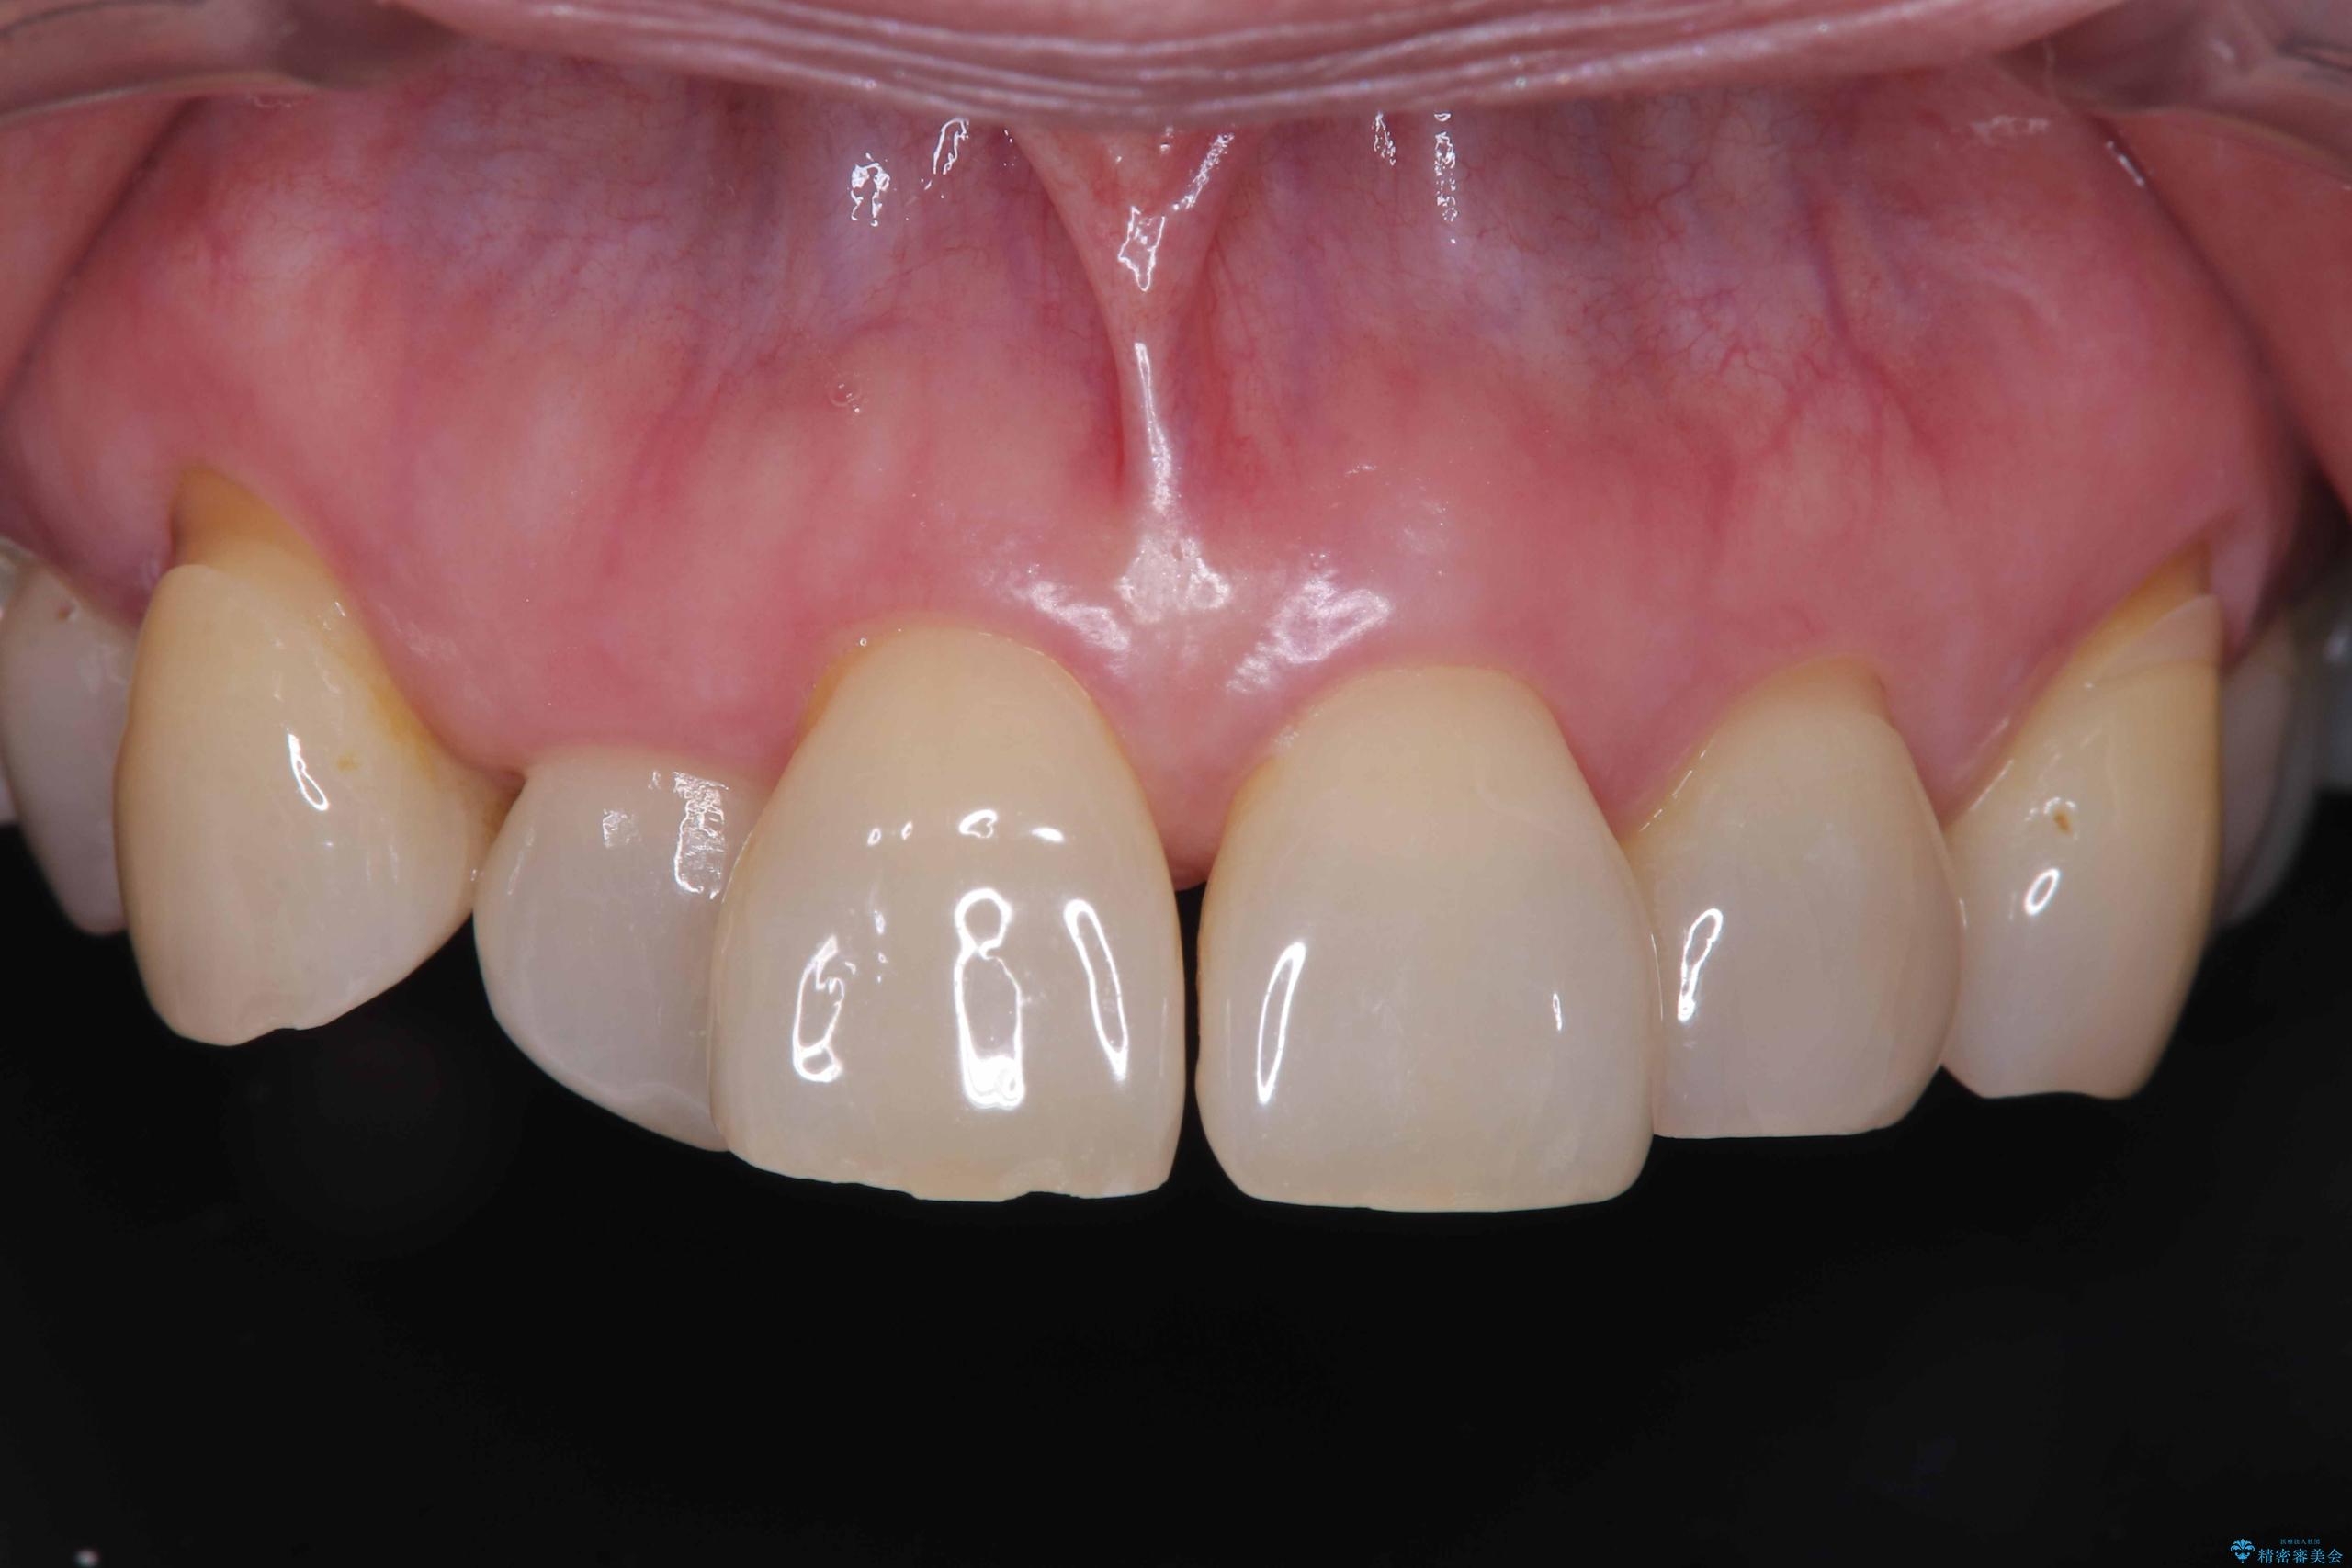

そのため今回は、右上2番を抜歯し、右上1番および左上1番をオールセラミッククラウンで審美的に修復しました。

治療期間も短く、抜歯からわずか3か月でオールセラミッククラウンを装着することができます。

また、オペ当日には仮歯まで装着するため、見た目を気にせず普段通りの生活を送ることができます。